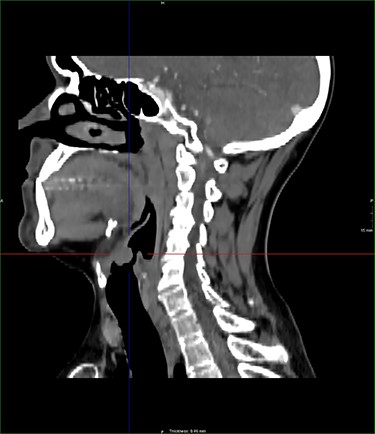

A laryngeal abnormality was noted, and he was referred to ENT for further assessment (Fig. 1). Flexible nasendoscopy showed a lesion on the laryngeal surface of the epiglottis in the midline. Vocal cords were not affected, although the lesion was extending close to the anterior commissure. An 18 × 14-mm lesion was found on magnetic resonance imaging (MRI) at the right paracentral supraglottic region, crossing the midline with possible involvement of the base of epiglottis (Fig. 2). There was no destruction of the thyroid cartilage or hyoid bone, and no involvement of the para-epiglottic space or glottis. There were no pathological cervical lymph nodes. Further CT scanning of the neck and chest confirmed the above, with no lung metastases identified (Figs 3 and 4).

sagittal postcontrast CT images of the neck with similar lesion related to the base of epiglottis, no involvement of the pre epiglottic fat.